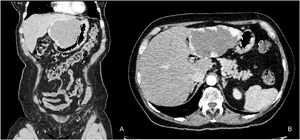

The patient was referred to our hospital for epigastric pain of two-year progression. Liver hemangioma was diagnosed through a tomography scan, with the characteristic uptake of contrast medium, involving segments II and III, and measuring 95 × 98 × 90 mm (Fig. 1A and B).

Laboratory test results showed hemoglobin 14.9 g/dL, hematocrit 44.5%, leukocytes 10,700 cells/µL, platelets 233,000 cells/µL, glucose 101 mg/dL, creatinine 0.71 mg/dL, sodium 142 mEq/L, potassium 3.9 mEq/L, alanine aminotransferase 15 U/L, aspartate aminotransferase 16 U/L, lactate dehydrogenase 293, total bilirubin 0.56 mg/dL, prothrombin time 13.2 s, partial thromboplastin time 27.5 s, and INR 0.98.